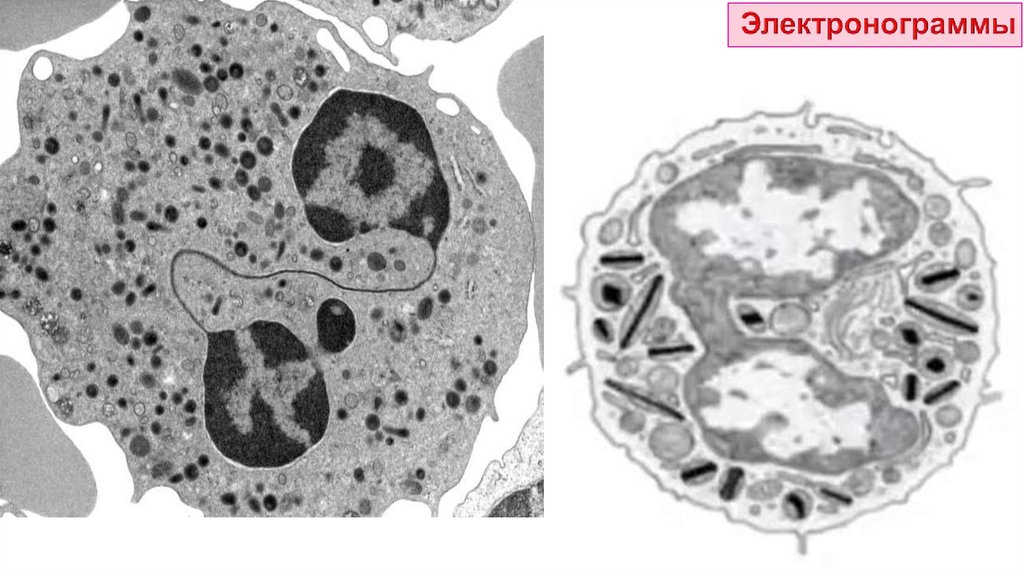

А – лимфоцит

Б – моноцит

Особенности:

• имеют НЕсегментированные ядра

• НЕ содержат специфических гранул

• заканчивают свою дифференцировку в тканях

Строение:

Ядро:

расположено эксцентрично

занимает большую часть клетки

содержит плотно упакованный

хроматин

Цитоплазма:

содержит азурофильные гранулы

(мелкие лизосомы)

богата рибосомами

Роль: обеспечение реакций

Лимфоцит:

1 – ядро

2 – рибосомы

3 – грЭПС

4 – митохондрии